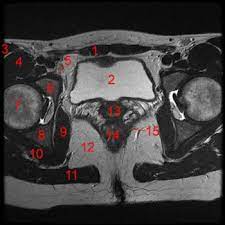

Pelvis Cross Sectional Mri Imagelarge Jpg 550 406 Diagnostic Imaging Mri Radiology Imaging

Pelvis Cross Sectional Mri Imagelarge Jpg 550 406 Diagnostic Imaging Mri Radiology Imaging from i.pinimg.com